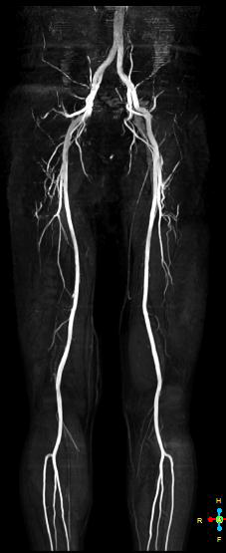

※下肢MRI画像